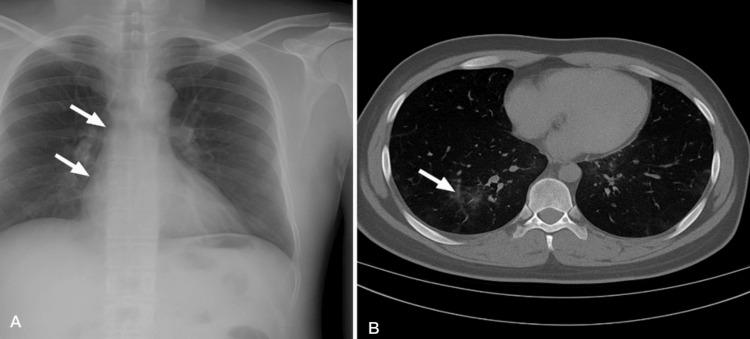

is a Gram-negative opportunistic pathogen increasingly encountered in hospital environments, particularly in intensive care units (ICUs), where it presents a major clinical challenge due to its multidrug-resistant (MDR) profile. Its resistance to multiple antibiotic classes makes it a serious therapeutic challenge, particularly in post-surgical patients where symptoms may be atypical. We report a case of a previously healthy 64-year-old male patient with a history of hypertension and coronary artery disease, admitted to the ICU following elective abdominal aortic aneurysm repair. On postoperative day five, he developed mild respiratory symptoms, low-grade fever, and oxygen desaturation, but with no abnormal lung auscultation findings. Elevated inflammatory markers and radiologic evidence of faint bilateral perihilar infiltrates and subtle ground-glass opacities prompted further investigation. Cultures revealed MDR resistant to carbapenems, aminoglycosides, and fluoroquinolones, but susceptible to colistin and tigecycline. The patient received combination intravenous therapy with colistin and tigecycline, resulting in rapid clinical improvement, normalization of inflammatory markers, and complete radiologic resolution by day 14. This case underscores the importance of maintaining a high index of suspicion for MDR pneumonia in post-surgical ICU patients with non-specific symptoms and highlights the role of early diagnosis and targeted therapy in achieving favorable outcomes.

是一种革兰氏阴性机会致病菌,在医院环境中越来越常见,尤其是在重症监护病房(ICU),由于其多重耐药(MDR)特性,它带来了重大的临床挑战。它对多种抗生素类别的耐药性使其成为一个严重的治疗难题,特别是在症状可能不典型的术后患者中。我们报告一例病例,一名64岁既往健康的男性患者,有高血压和冠状动脉疾病史,在择期腹主动脉瘤修复术后入住ICU。术后第5天,他出现轻度呼吸道症状、低热和氧饱和度下降,但肺部听诊无异常发现。炎症标志物升高以及双侧肺门周围模糊浸润和细微磨玻璃影的影像学证据促使进一步检查。培养结果显示该菌对碳青霉烯类、氨基糖苷类和氟喹诺酮类耐药,但对黏菌素和替加环素敏感。患者接受了黏菌素和替加环素联合静脉治疗,14天时临床迅速改善,炎症标志物恢复正常,影像学完全恢复。该病例强调了对术后ICU出现非特异性症状的患者高度怀疑MDR肺炎的重要性,并突出了早期诊断和靶向治疗在取得良好结局中的作用。